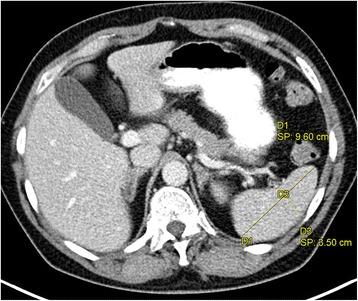

In radiology, a vast amount of diverse data is generated, and unstructured reporting is standard. Hence, much useful information is trapped in free-text form, and often lost in translation and transmission. One relevant source of free-text data consists of reports covering the assessment of changes in tumor burden, which are needed for the evaluation of cancer treatment success. Any change of lesion size is a critical factor in follow-up examinations. It is difficult to retrieve specific information from unstructured reports and to compare them over time. Therefore, a prototype was implemented that demonstrates the structured representation of findings, allowing selective review in consecutive examinations and thus more efficient comparison over time.

We developed a semantic Model for Clinical Information (MCI) based on existing ontologies from the Open Biological and Biomedical Ontologies (OBO) library. MCI is used for the integrated representation of measured image findings and medical knowledge about the normal size of anatomical entities. An integrated view of the radiology findings is realized by a prototype implementation of a ReportViewer. Further, RECIST (Response Evaluation Criteria In Solid Tumors) guidelines are implemented by SPARQL queries on MCI. The evaluation is based on two data sets of German radiology reports: An oncologic data set consisting of 2584 reports on 377 lymphoma patients and a mixed data set consisting of 6007 reports on diverse medical and surgical patients. All measurement findings were automatically classified as abnormal/normal using formalized medical background knowledge, i.e., knowledge that has been encoded into an ontology. A radiologist evaluated 813 classifications as correct or incorrect. All unclassified findings were evaluated as incorrect.

The proposed approach allows the automatic classification of findings with an accuracy of 96.4 % for oncologic reports and 92.9 % for mixed reports. The ReportViewer permits efficient comparison of measured findings from consecutive examinations. The implementation of RECIST guidelines with SPARQL enhances the quality of the selection and comparison of target lesions as well as the corresponding treatment response evaluation.

在放射学领域,会产生大量多样的数据,非结构化报告是标准形式。因此,许多有用信息以自由文本形式存在,且常常在翻译和传输过程中丢失。自由文本数据的一个相关来源是涵盖肿瘤负荷变化评估的报告,这对于评估癌症治疗效果是必需的。病变大小的任何变化都是随访检查中的关键因素。从非结构化报告中检索特定信息并随时间进行比较很困难。因此,实现了一个原型,该原型展示了检查结果的结构化表示,允许在连续检查中进行选择性回顾,从而更有效地随时间进行比较。

我们基于开放生物和生物医学本体(OBO)库中的现有本体开发了临床信息语义模型(MCI)。MCI用于测量图像结果和关于解剖实体正常大小的医学知识的综合表示。通过ReportViewer的原型实现实现了放射学检查结果的综合视图。此外,通过对MCI的SPARQL查询实现了实体瘤疗效评价标准(RECIST)指南。评估基于两组德国放射学报告数据集:一组肿瘤学数据集,包含377例淋巴瘤患者的2584份报告;一组混合数据集,包含不同医学和外科患者的6007份报告。所有测量结果均使用形式化医学背景知识(即已编码到本体中的知识)自动分类为异常/正常。一名放射科医生将813个分类评估为正确或不正确。所有未分类的结果均评估为不正确。

所提出的方法允许对检查结果进行自动分类,肿瘤学报告的准确率为96.4%,混合报告的准确率为92.9%。ReportViewer允许对连续检查中的测量结果进行有效比较。通过SPARQL实施RECIST指南提高了靶病变选择和比较以及相应治疗反应评估的质量。